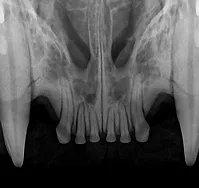

Dental care is essential to an animal’s overall health. Knowing how to properly identify and treat oral disease is crucial in the well-being of your patients. The American Veterinary Dental Society has reported that the majority of cats and dogs have periodontal health issues by the age of three. Many oral problems are not visible above the gum-line and can be overlooked without the right education. Untreated or misdiagnosed dental problems are the source of chronic pain and infection.